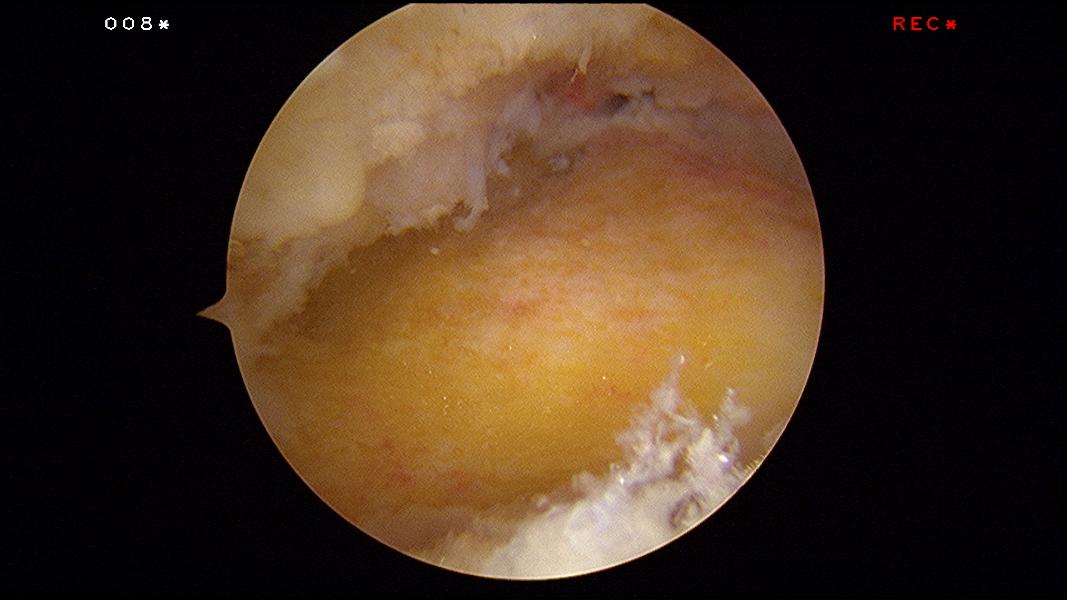

A 4.0mm hooded arthroscopic burr is used to remove the Haglund’s exostosis. All of the time the opening of the burr is facing the bone. The foot is placed in full plantarflexion and the posterior superior bone rim can be removed.

Upon completion of the procedure, the exostosis should be flattened and the insertion of the Achilles tendon into the heel bone should be clearly seen.

An intra-operative fluroscopy (x-rays) is taken to confirm complete removal of the Haglund’s protruberance.